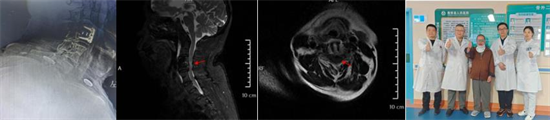

術(shù)后復(fù)查顯示內(nèi)固定位置良好、椎管減壓充分,患者自覺癥狀明顯緩解

為確保手術(shù)成功,骨科二區(qū)專家團(tuán)隊(duì)與湘雅三醫(yī)院苗驚雷教授緊密協(xié)作,在麻醉科和手術(shù)室的配合下,成功為患者實(shí)施頸前路椎間盤切除術(shù)+椎管擴(kuò)大減壓術(shù)+植骨融合內(nèi)固定術(shù),患者術(shù)后即感四肢肌力明顯改善,目前恢復(fù)良好,已順利出院。